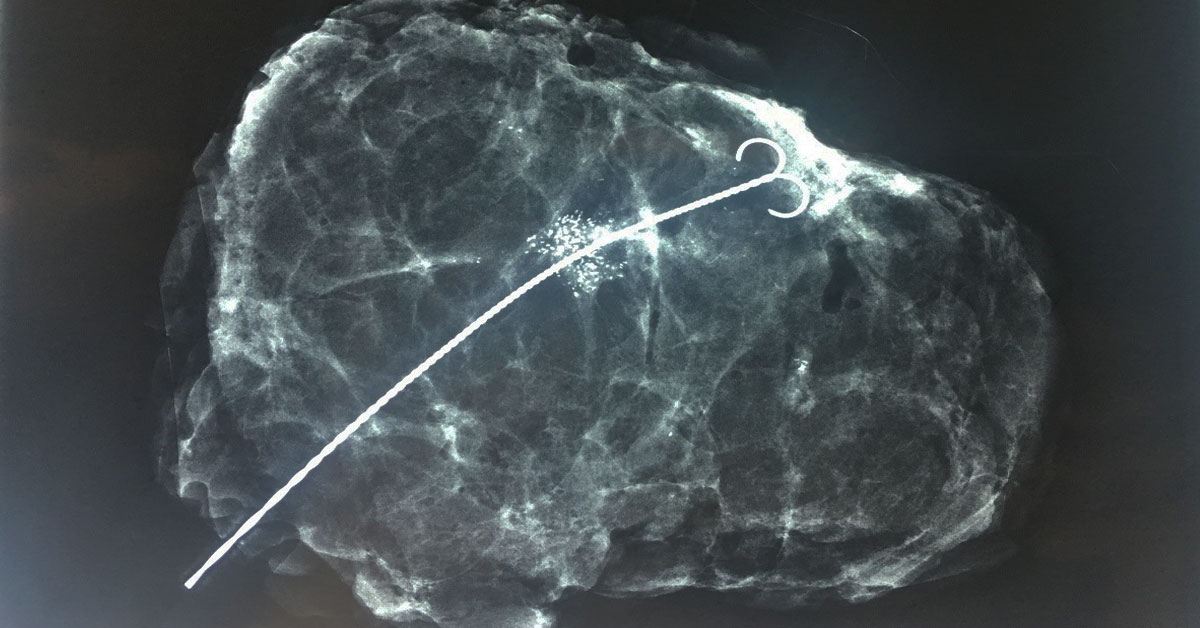

Αν κάποιο εύρημα που πρέπει να αφαιρεθεί δεν είναι ψηλαφητό, ο χειρουργός χρειάζεται σήμανση, ώστε να προβεί στην αφαίρεση της περιοχής ενδιαφέροντος. Η τοποθέτηση χειρουργικού οδηγού περιλαμβάνει την τοποθέτηση ενός λεπτού σύρματος εντός του μαστού με το άκρο του τοποθετημένο στην περιοχή του ύποπτου ευρήματος.

Πριν από το χειρουργείο, ένας ειδικός ακτινοδιαγνώστης τοποθετεί τον συρμάτινο οδηγό στη σωστή θέση με τη χρήση υπερηχογραφικής ή μαστογραφικής καθοδήγησης.

Λαμβάνονται μαστογραφικές λήψεις ώστε να ενημερωθεί ο χειρουργός για τη σωστή θέση του χειρουργικού οδηγού εντός του μαστού (η μαστογραφία παρέχει στον χειρουργό καλύτερη εικόνα για τη θέση του χειρουργικού οδηγού σε σχέση με το υπερηχογράφημα).

Ο ακτινοδιαγνώστης τοποθετεί μια λεπτή βελόνα στην περιοχή του μαστού που πρέπει να αφαιρεθεί. Λαμβάνονται μαστογραφικές λήψεις ώστε να επιβεβαιωθεί η σωστή θέση του χειρουργικού οδηγού εντός του μαστού.

Ένα τμήμα του λεπτού συρμάτινου οδηγού παραμένει εκτός του μαστού. Μετά το τέλος της διαδικασίας το τμήμα του χειρουργικού οδηγού που παραμένει εκτός του μαστού, ακινητοποιείται, ενώ το εσωτερικό τμήμα παραμένει στην περιοχή που πρέπει να αφαιρεθεί.

Οι προηγούμενες απεικονίσεις και οι εικόνες μετά την τοποθέτηση του χειρουργικού οδηγού αποστέλλονται στον χειρουργό.